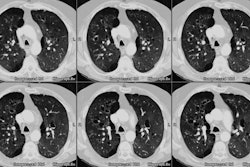

Bronchiolitis obliterans:

The patient shown below had experienced a severe right lower lobe haemophilus influenza pneumonia the preceding year, but had persistent pulmonary complains. The inspiratory CT images reveal bronchiectatic changes involving the bronchi to the anterior and medial basal segments of the right lower lobe (yellow arrows). Expiratory images deomstrate air trapping in these same segments (white arrows). Air trapping is also evident in the medial segment of the right middle lobe. The findings are consistent with post-infectious bronchiolitis obliterans.